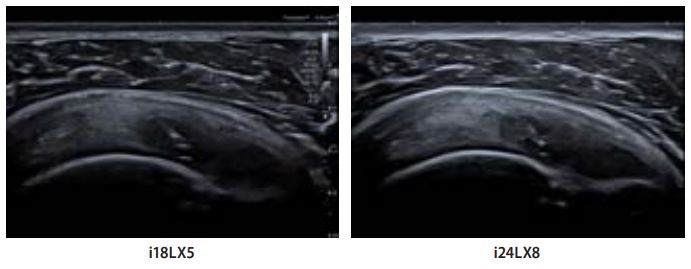

Колишній гравець у крикет скаржився на постійний біль у плечі. За допомогою i18LX5 було виявлено розрив надвиросткової поверхні плечової кістки часткової ширини, та часткової товщини. Однак за допомогою i24LX5 структури тканин і розрив були окреслені з більшою деталізацією і чіткістю. Висока роздільна здатність надвисокочастотного датчика забезпечує більшу діагностичну достовірність, усуваючи необхідність подальшої діагностики, і, таким чином, дозволяє негайно призначити відповіднелікування.

Мал. 3.

Випадок 2: сухожилля надвиросткового м'яза та субакроміальний субдельтоподібний бурсит

i18LX5 демонструє детальні структури з хорошим проникненням, що дозволяє оператору швидко провести це планове обстеження з високою діагностичною достовірністю. i24LX8 демонструє значно підвищену деталізацію тканин у ближньому полі та достатнє проникнення через все сухожилля надвиросткового м'яза, що дозволяє проводити клінічну діагностику. Ці парні зображення демонструють можливості як i18LX5, так і адекватну глибину проникнення надвисокочастотного датчика i24LX8, що дозволяє використовувати його для загальної візуалізації опорно-рухового апарату.

Мал. 4.